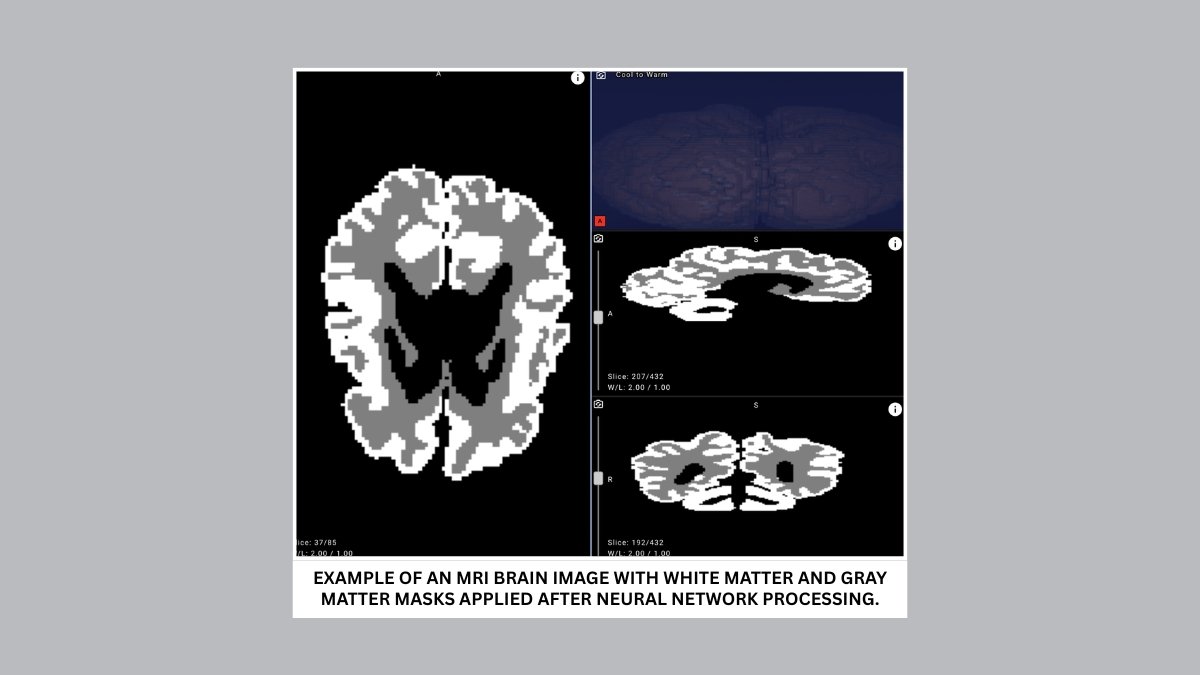

The proposed solution analyzes MRI scans and can distinguish between gray and white brain matter with over 90% accuracy. Cutting evaluation time from days to minutes, it enables earlier detection and more effective rehabilitation planning for infants with cerebral palsy and other central nervous system disorders.

To bridge this gap, Yandex researchers collaborated with medical experts to create new annotations, design a dedicated neural network architecture, and run a series of machine learning experiments. The resulting model achieved over 90% accuracy in distinguishing gray and white matter in infant brains on internal evaluation data, demonstrating its potential for clinical use.

- Improve accuracy and objectivity. With over 90% accuracy, the model highlights outlines and quantifies the ratio of gray to white matter in an infant’s brain.